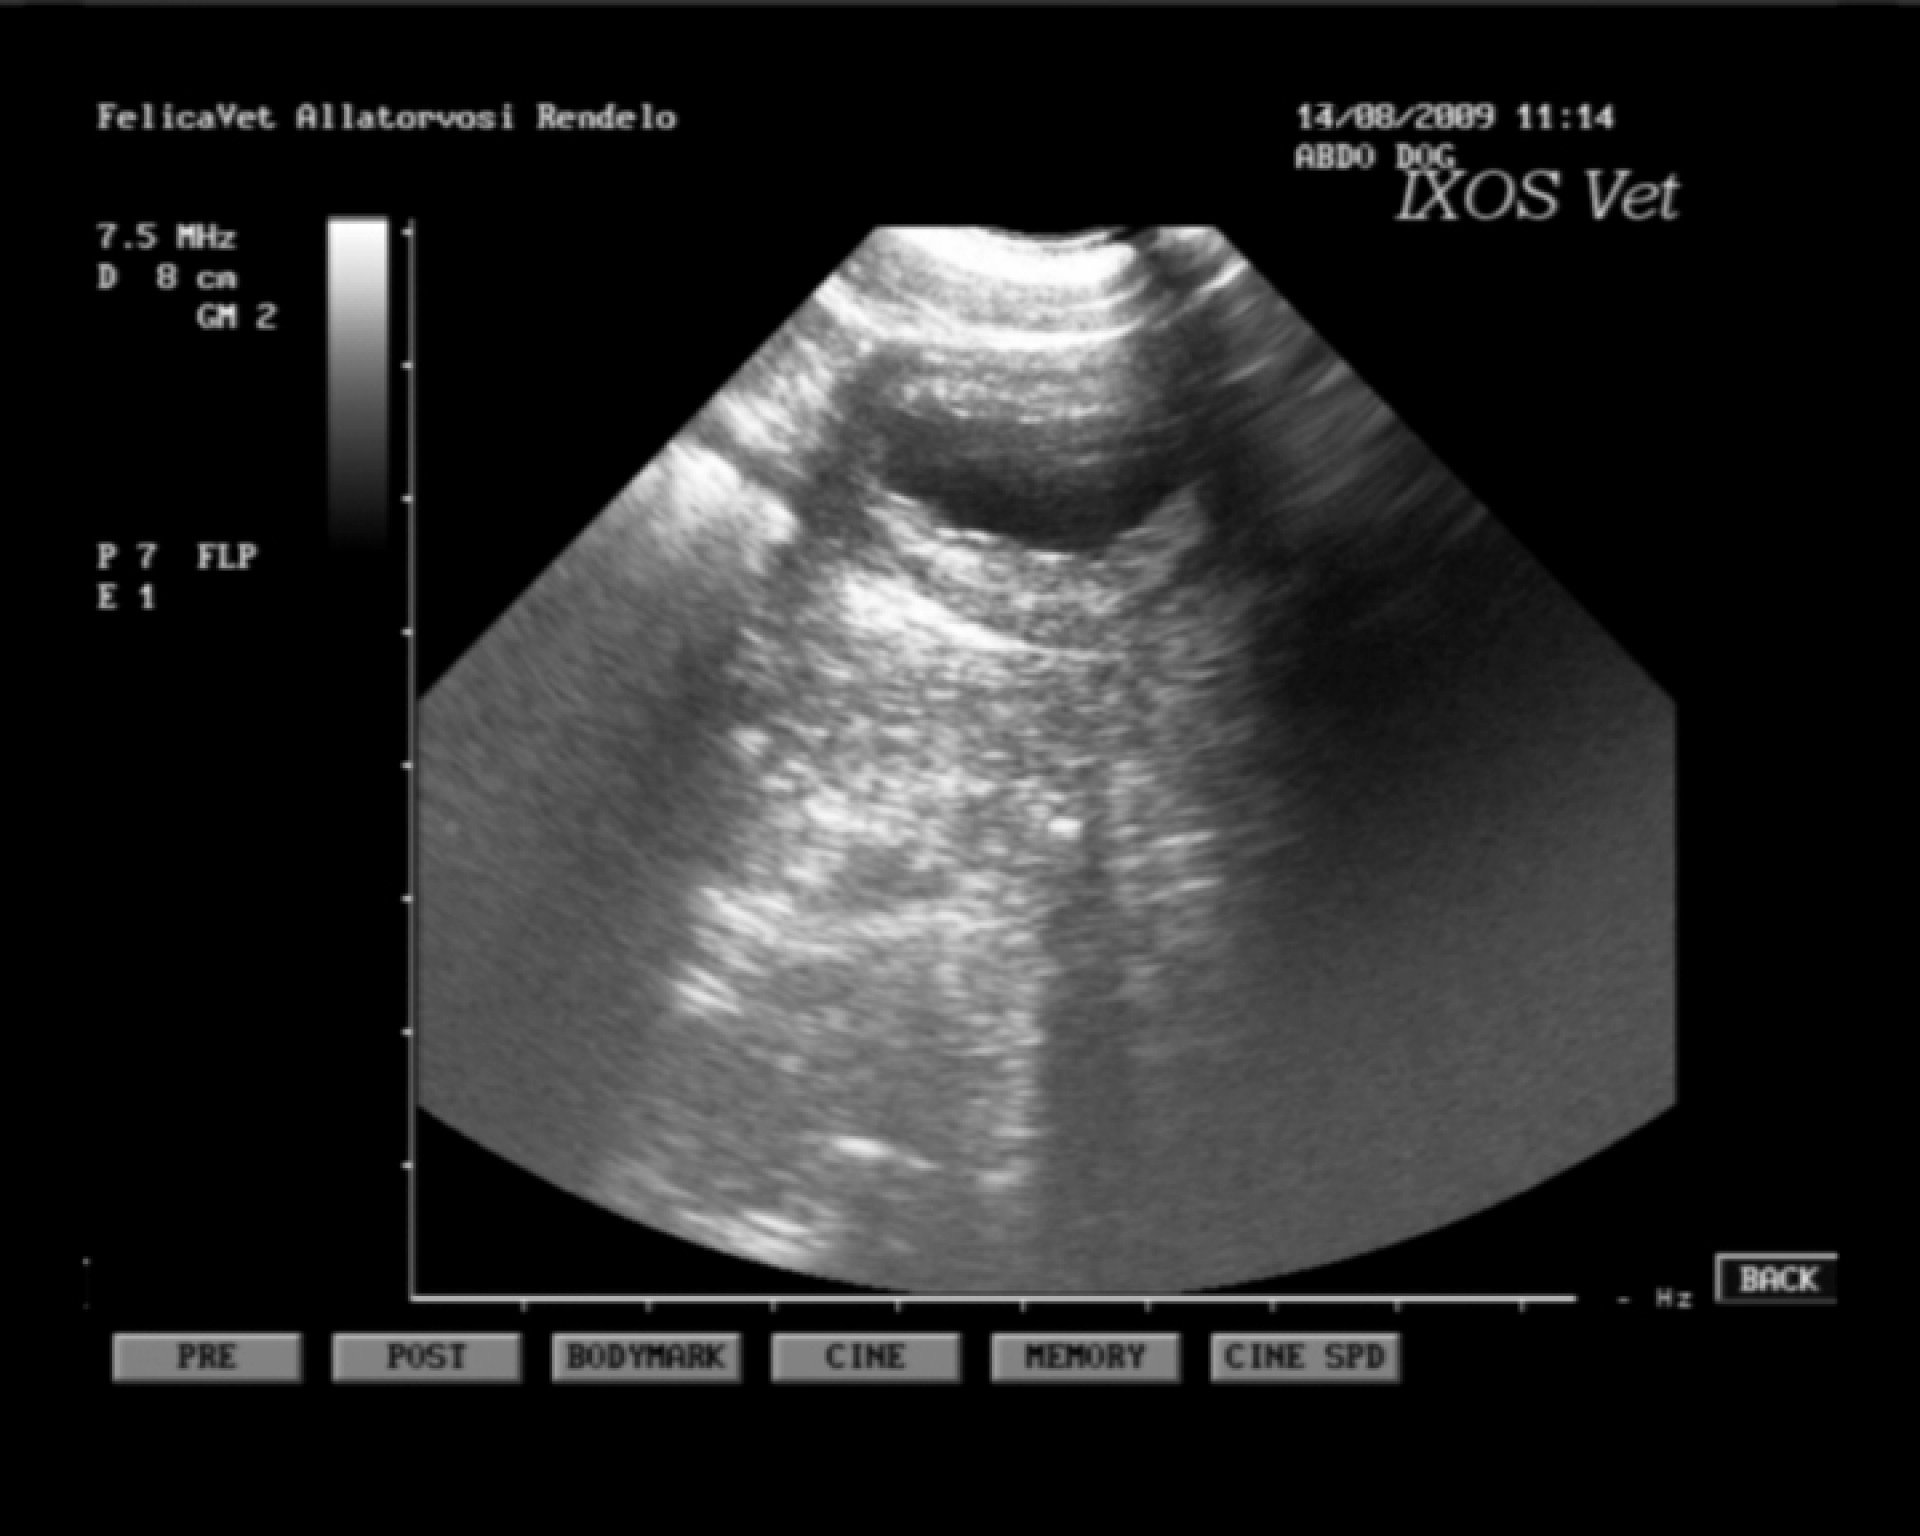

Bár magam nem vagyok az ultrahang diagnosztikában különösebben jártas, a hasüreg vizsgálata során vizelettel telt hólyagot, normális szerkezetű veséket és egy jelentősen megnagyobbodott lépet találtam.

A lép Doppler vizsgálatával a szerv vérkeringésének teljes hiánya volt igazolható.